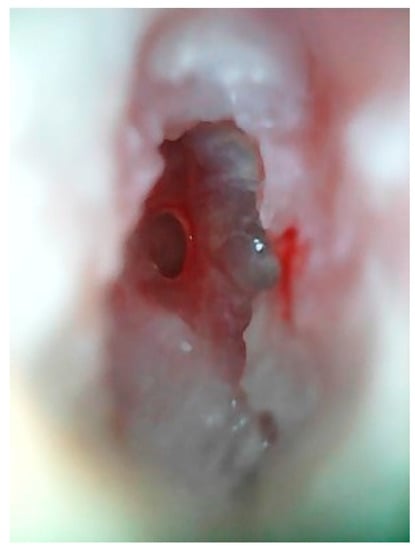

3.1. Patient 1

3.2. Patient 2

3.3. Patient 3